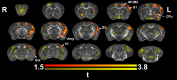

We do not have a full understanding of the mechanisms underlying plasticity in the human brain. Mouse models have well controlled environments and genetics, and provide tools to help dissect the mechanisms underlying the observed responses to therapies devised for humans recovering from injury of ischemic nature or trauma. We aimed to detect plasticity following learning of a unilateral reaching movement, and relied on MRI performed with a rapid structural protocol suitable for in vivo brain imaging, and a longer diffusion tensor imaging (DTI) protocol executed ex vivo. In vivo MRI detected contralateral volume increases in trained animals (reachers), in circuits involved in motor control, sensory processing, and importantly, learning and memory. The temporal association area, parafascicular and mediodorsal thalamic nuclei were also enlarged. In vivo MRI allowed us to detect longitudinal effects over the ~25 days training period. The interaction between time and group (trained versus not trained) supported a role for the contralateral, but also the ipsilateral hemisphere. While ex vivo imaging was affected by shrinkage due to the fixation, it allowed for superior resolution and improved contrast to noise ratios, especially for subcortical structures. We examined microstructural changes based on DTI, and identified increased fractional anisotropy and decreased apparent diffusion coefficient, predominantly in the cerebellum and its connections. Cortical thickness differences did not survive multiple corrections, but uncorrected statistics supported the contralateral effects seen with voxel based volumetric analysis, showing thickening in the somatosensory, motor and visual cortices. In vivo and ex vivo analyses identified plasticity in circuits relevant to selecting actions in a sensory-motor context, through exploitation of learned association and decision making. By mapping a connectivity atlas into our ex vivo template we revealed that changes due to skilled motor learning occurred in a network of 35 regions, including the primary and secondary motor (M1, M2) and sensory cortices (S1, S2), the caudate putamen (CPu), visual (V1) and temporal association cortex. The significant clusters intersected tractography based networks seeded in M1, M2, S1, V1 and CPu at levels > 80%. We found that 89% of the significant cluster belonged to a network seeded in the contralateral M1, and 85% to one seeded in the contralateral M2. Moreover, 40% of the M1 and S1 cluster by network intersections were in the top 80th percentile of the tract densities for their respective networks. Our investigation may be relevant to studies of rehabilitation and recovery, and points to widespread network changes that accompany motor learning that may have potential applications to designing recovery strategies following brain injury.